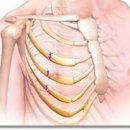

날씬해질 수 있다면…美서 유행하는 갈비뼈 재조정 시술 2025.12.04해당카페글 미리보기

출처: https://v.daum.net/v/20251204151746209 날씬해질 수 있다면…美서 유행하는 갈비뼈 재조정 시술 최근 미국에서는 더욱 날씬한 허리를 갖기 위해 갈비뼈를 제거하거나 위치를 조정하는 시술이 유행하고 있다. 3일(현지시간) 뉴욕포스트에 따르면...